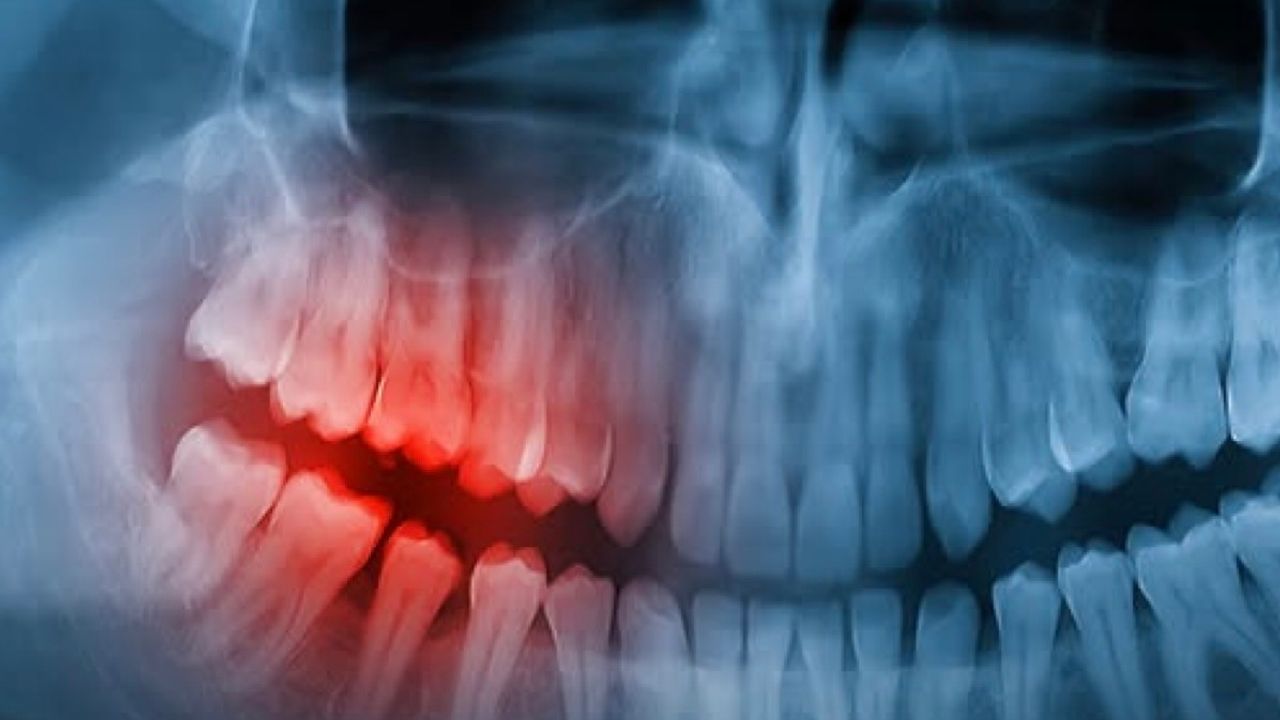

Bilim insanları, diş gelişimini baskıladığı bilinen USAG-1 (uterine sensitization associated gene-1) adlı proteinin etkisini azaltmayı hedefleyen bir antikor tedavisi üzerinde çalışıyor. Hayvan deneylerinde bu proteinin baskılanmasının yeni diş oluşumunu tetikleyebildiği bildirilmişti. Şimdi bu yaklaşımın insanlar için güvenli ve etkili olup olmadığı araştırılıyor.

Embriyonik dönemde insanlarda üçüncü bir diş tomurcuğu dizisinin oluştuğu, ancak çoğunlukla gerileyip kaybolduğu biliniyor. Yeni ilaç yaklaşımı, bu gizli potansiyelin yeniden aktive edilmesine odaklanıyor. Araştırma ekibi, özellikle diş eksikliğiyle doğan hastalarda ve travma sonrası diş kaybı yaşayan kişilerde yeni seçenekler geliştirmeyi amaçlıyor.